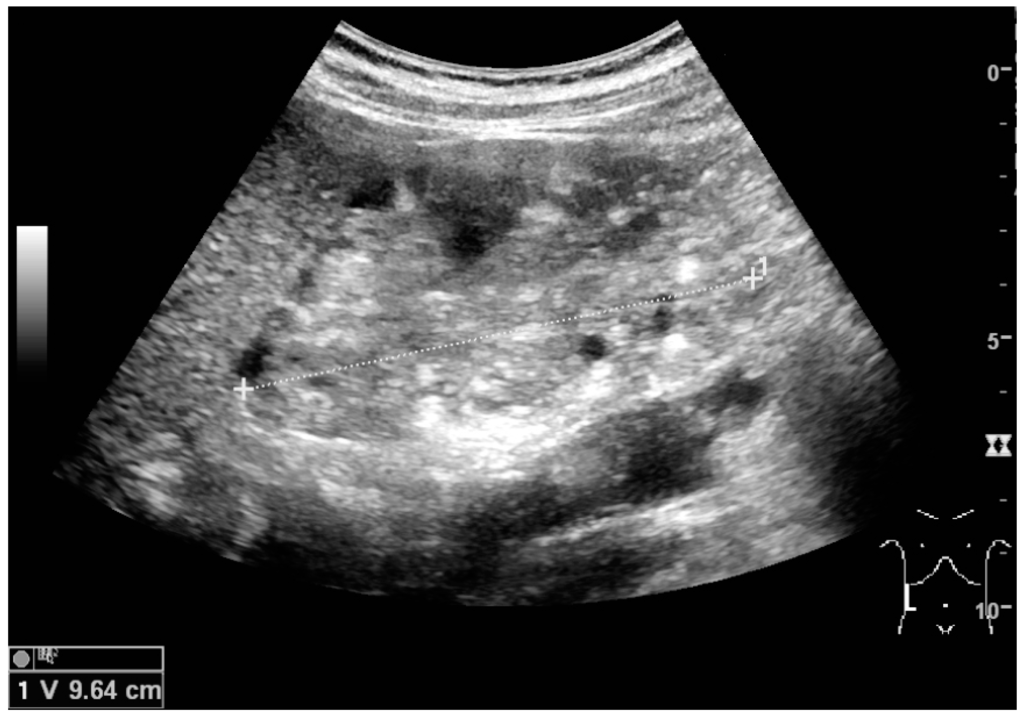

Benign solid tumors of the kidney are oncocytoma and angiomyofibroma. Oncocytoma has a varying ultrasonic appearance, but may have a central scar or calcification as a hallmark [21]. Angiomyofibroma are often found in patients with tuberous sclerosis. They are composed of fat, smooth muscle tissue and vascular elements. The echogenicity is governed by the composition of these elements, but the lesion is often hyperechoic (Figure 11 and Figure 12) [22].

Figure 12. Patient with tuberous sclerosis and multiple angiomyolipomas in the kidney. Measurement of kidney length on the US image is illustrated by ‘+’ and a dashed line.